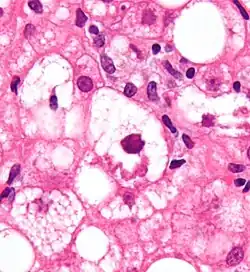

Corps de Mallory

En histopathologie, les corps de Mallory (ou Mallory–Denk body, MDB) sont des inclusions trouvées dans le cytoplasme des cellules du foie[1]. Ils portent le nom du pathologiste américain Frank Burr Mallory.

Les corps de Mallory entrent le plus souvent dans le cadre d'une hépatopathie alcoolique[2]. Ils représentent des amas résiduels de microfilaments consécutifs à la toxicité de l’alcool et de ses métabolites.

De manière plus générale, les corps de Mallory se retrouvent aussi dans une stéatohépatite non alcoolique[3]